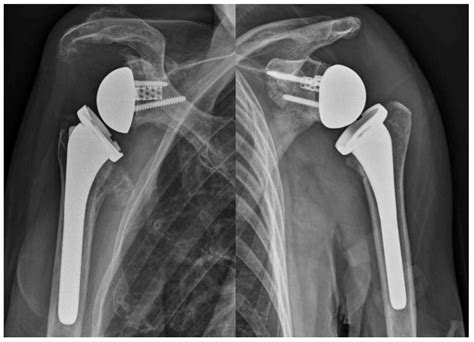

Computer-Assisted Navigation in Reverse Shoulder Arthroplasty: Surgical ...